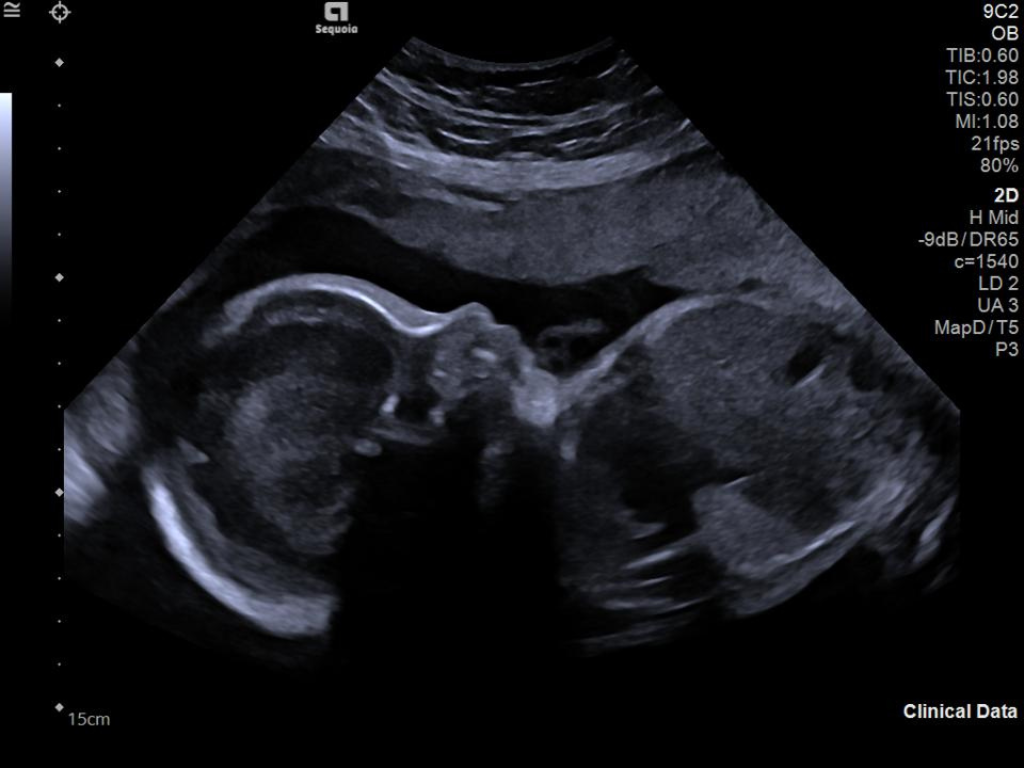

The ACUSON Sequoia is an advanced diagnostic tool that integrates cutting-edge technology and AI-powered applications to streamline diagnostic processes. This system is designed to cater to patient-specific needs, ensuring accuracy and efficiency in various clinical settings such as Radiology, OB/GYN, Shared Service and beyond.

A clearer, deeper perspective with optimal acoustics for each clinical use case. Expand your assessment with advanced tools that take ultrasound beyond its traditional role.

- AI Abdomen automatically recognizes and labels 17 anatomical views and 12 routine measurements.